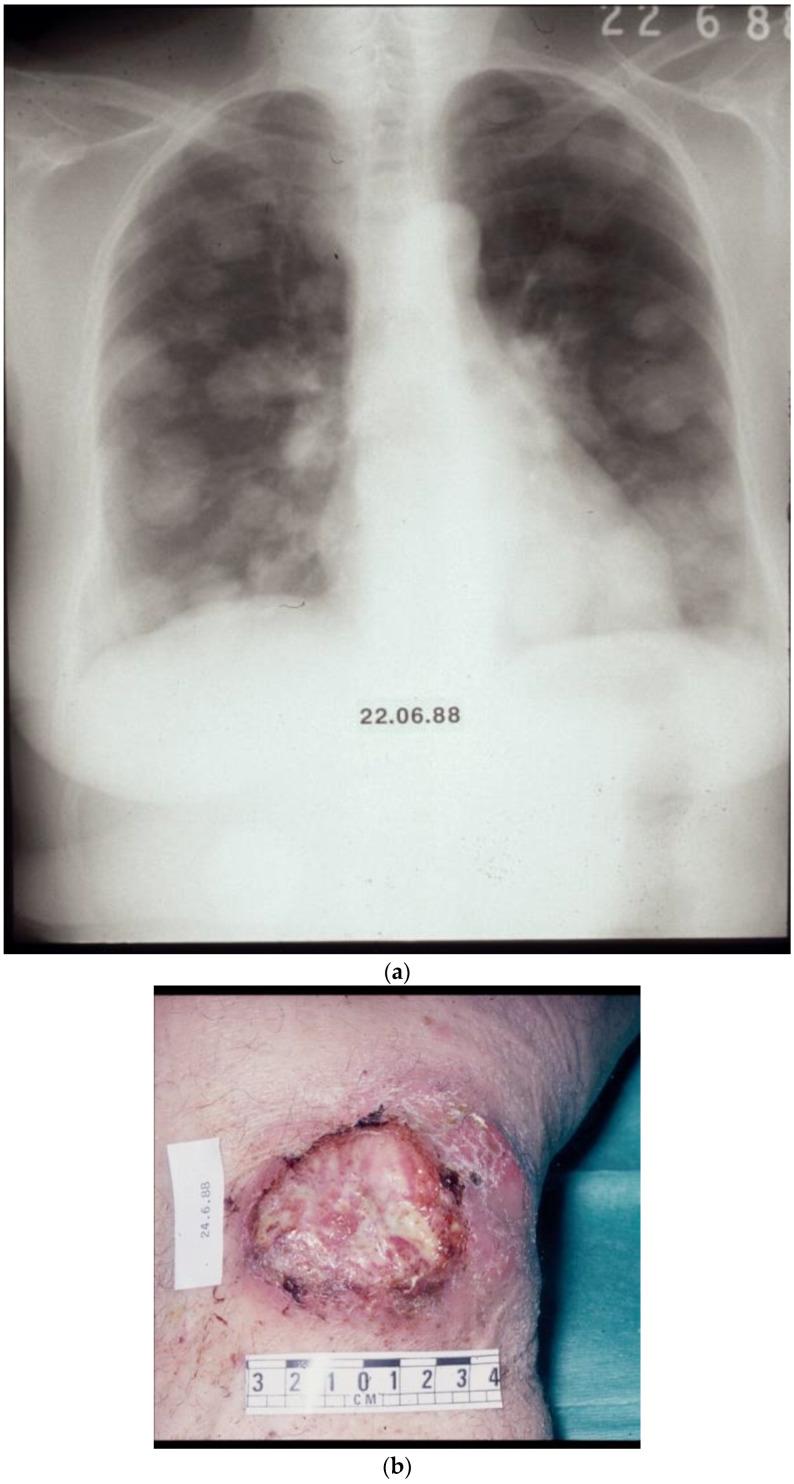

The unravelling of the human genome created new perceptions of the origin and evolution of diseases, and for cancer in particular, it established the notion that neoplasia has been a companion of life since its appearance on Earth. It is not surprising that neoplasms, in various forms, develop in numerous species of animals and even in plants. Unmistakable accounts of cancer with clinical features as are understood today begin in the 5th c. B.C. The principles and practice of the Hippocratic and Galenic tradition dominated cancer care virtually into the 20th century. Advanced sequencing technologies at the dawn of the 21st century generated new therapeutic opportunities with immunotherapy, oncolytic virotherapy, and gene transfer, with the latter especially being used in cases of hereditary cancer.